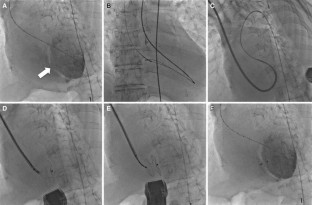

A 77-year-old woman underwent percutaneous closure of post-infarction ventricular septal defect. The defect was successfully closed with a 20-mm Amplatzer septal occluder with a small residual shunt and Qp/Qs improved from 3.38 to 1.48. She was discharged 30 days after procedure. To our knowledge, this is the first case reported in Japan.

Fig. 1